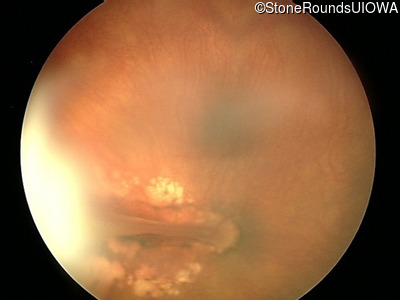

Visit at age: 23 months

Fundus Photography - Right - UCUSUM

Exemplar